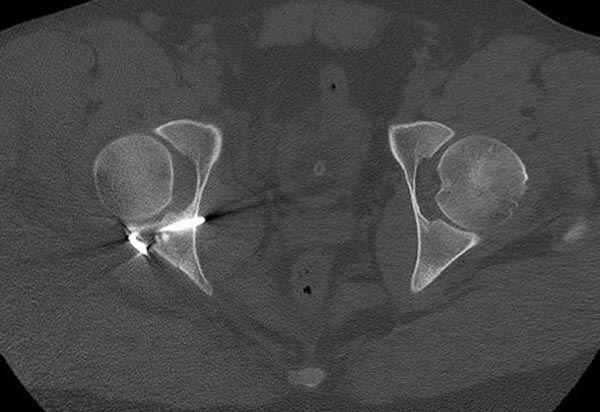

11:50 больной в послеоперационной, рентгенограмма N7, компьютерная томограмма в тот же день N8-10

Больные с ацетабулярными и тазовыми переломами, идущие на операцию, по протоколу исследуется до операции на состояния сосудистой системы доgплером, который повторяется после операции перед выпиской (были множество случаев позднего развития ДВТ в после операционном периоде)